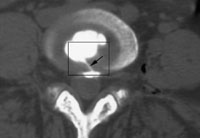

研究发现,椎间盘源性下腰痛病人的疼痛椎间盘在组织学上的显著特征表现为形成一条从髓核至纤维环外层的血管化肉芽组织条带区,肉芽组织成熟程度不一,其间伴有1个或多个裂隙(如图);P物质、神经丝蛋白和血管活性肠肽三种神经肽阳性神经纤维明显增多,且主要沿伴有裂隙的肉芽组织条带区分布。据此他推断,椎间盘后方神经分布广泛的肉芽组织条带区是椎间盘源性下腰痛的起源部位,外来压力作用于该部位是引起椎间盘性源下腰痛的主要原因。, 百拇医药